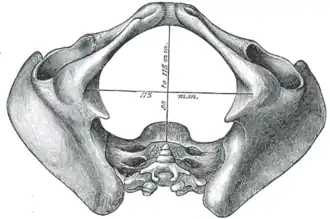

Pelvic outlet

Diameters of inferior aperture of lesser pelvis (female) | |

The lower circumference of the lesser pelvis is very irregular; the space enclosed by it is named the inferior aperture or pelvic outlet. It is an important component of pelvimetry.

Boundaries

It has the following boundaries:

- anteriorly: the pubic arch

- laterally: the ischial tuberosities

- posterolaterally: the inferior margin of the sacrotuberous ligament

- posteriorly: the anterior border of the middle of the coccyx.[1]

In situ

When the ligaments are in situ, the inferior aperture of the pelvis is lozenge-shaped, bounded as follows:

- in front, by the pubic arcuate ligament and the inferior rami of the pubes and ischia

- laterally, by the ischial tuberosities

- behind, by the sacrotuberous ligaments and the tip of the coccyx.

Intertuberous diameter, as a measure of the transverse measure of the pelvic outlet

Intertuberous diameter, as a measure of the transverse measure of the pelvic outlet